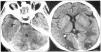

Acudió a emergencias de nuestro centro en agosto de 1999 por edemas maleolares de una semana de evolución, con cefalea occipital, somnolencia y pérdida de agudeza visual en los tres días previos a la consulta. En la exploración física inicial destacaron edemas maleolares y TA de 170/130 mmHg. Estando en emergencias presentó crisis comicial tonicoclónica generalizada seguida de disminución del nivel de consciencia y movimientos de descerebración, procediéndose a intubación orotraqueal (IOT) y a ventilación mecánica (VM). En la anamg/dla inicial destacó urea de 200 mg/di y creatinina de 4 mg/dl, con CK normales, siendo el resto de parámetros normales. El análisis toxicológico fue positivo para cocaína, benzodiacepinas, metoclopramida y posibles opiáceos. Una TAC cerebral demostró lesiones isquémicas, de baja perfusión sanguínea, occipitales y cerebelosas (figura 1).

La evolución posterior mostró una colostasis disociada con elevación importante de fosfatasas alcalinas y gammaGT pero con bilirrubina normal. Una nueva ecografía abdominal no mostró alteraciones destacables y una colangio-resonancia magnética sólo puso de manifiesto unas imágenes compatibles con hemangiomas hepáticos. La determinación de criptosporidium en heces fue negativa. Se atribuyó el cuadro a colangitis por citomegalovirus, evolucionando bien posteriormente sin la práctica de más exploraciones al respecto. También presentó un herpes esofágico que evolucionó bien con acyclovir. Una TAC cerebral de control mostró la resolución total de las lesiones de hipoperfusión de lóbulo cerebral occipital y de cerebelo.

Figura 1.